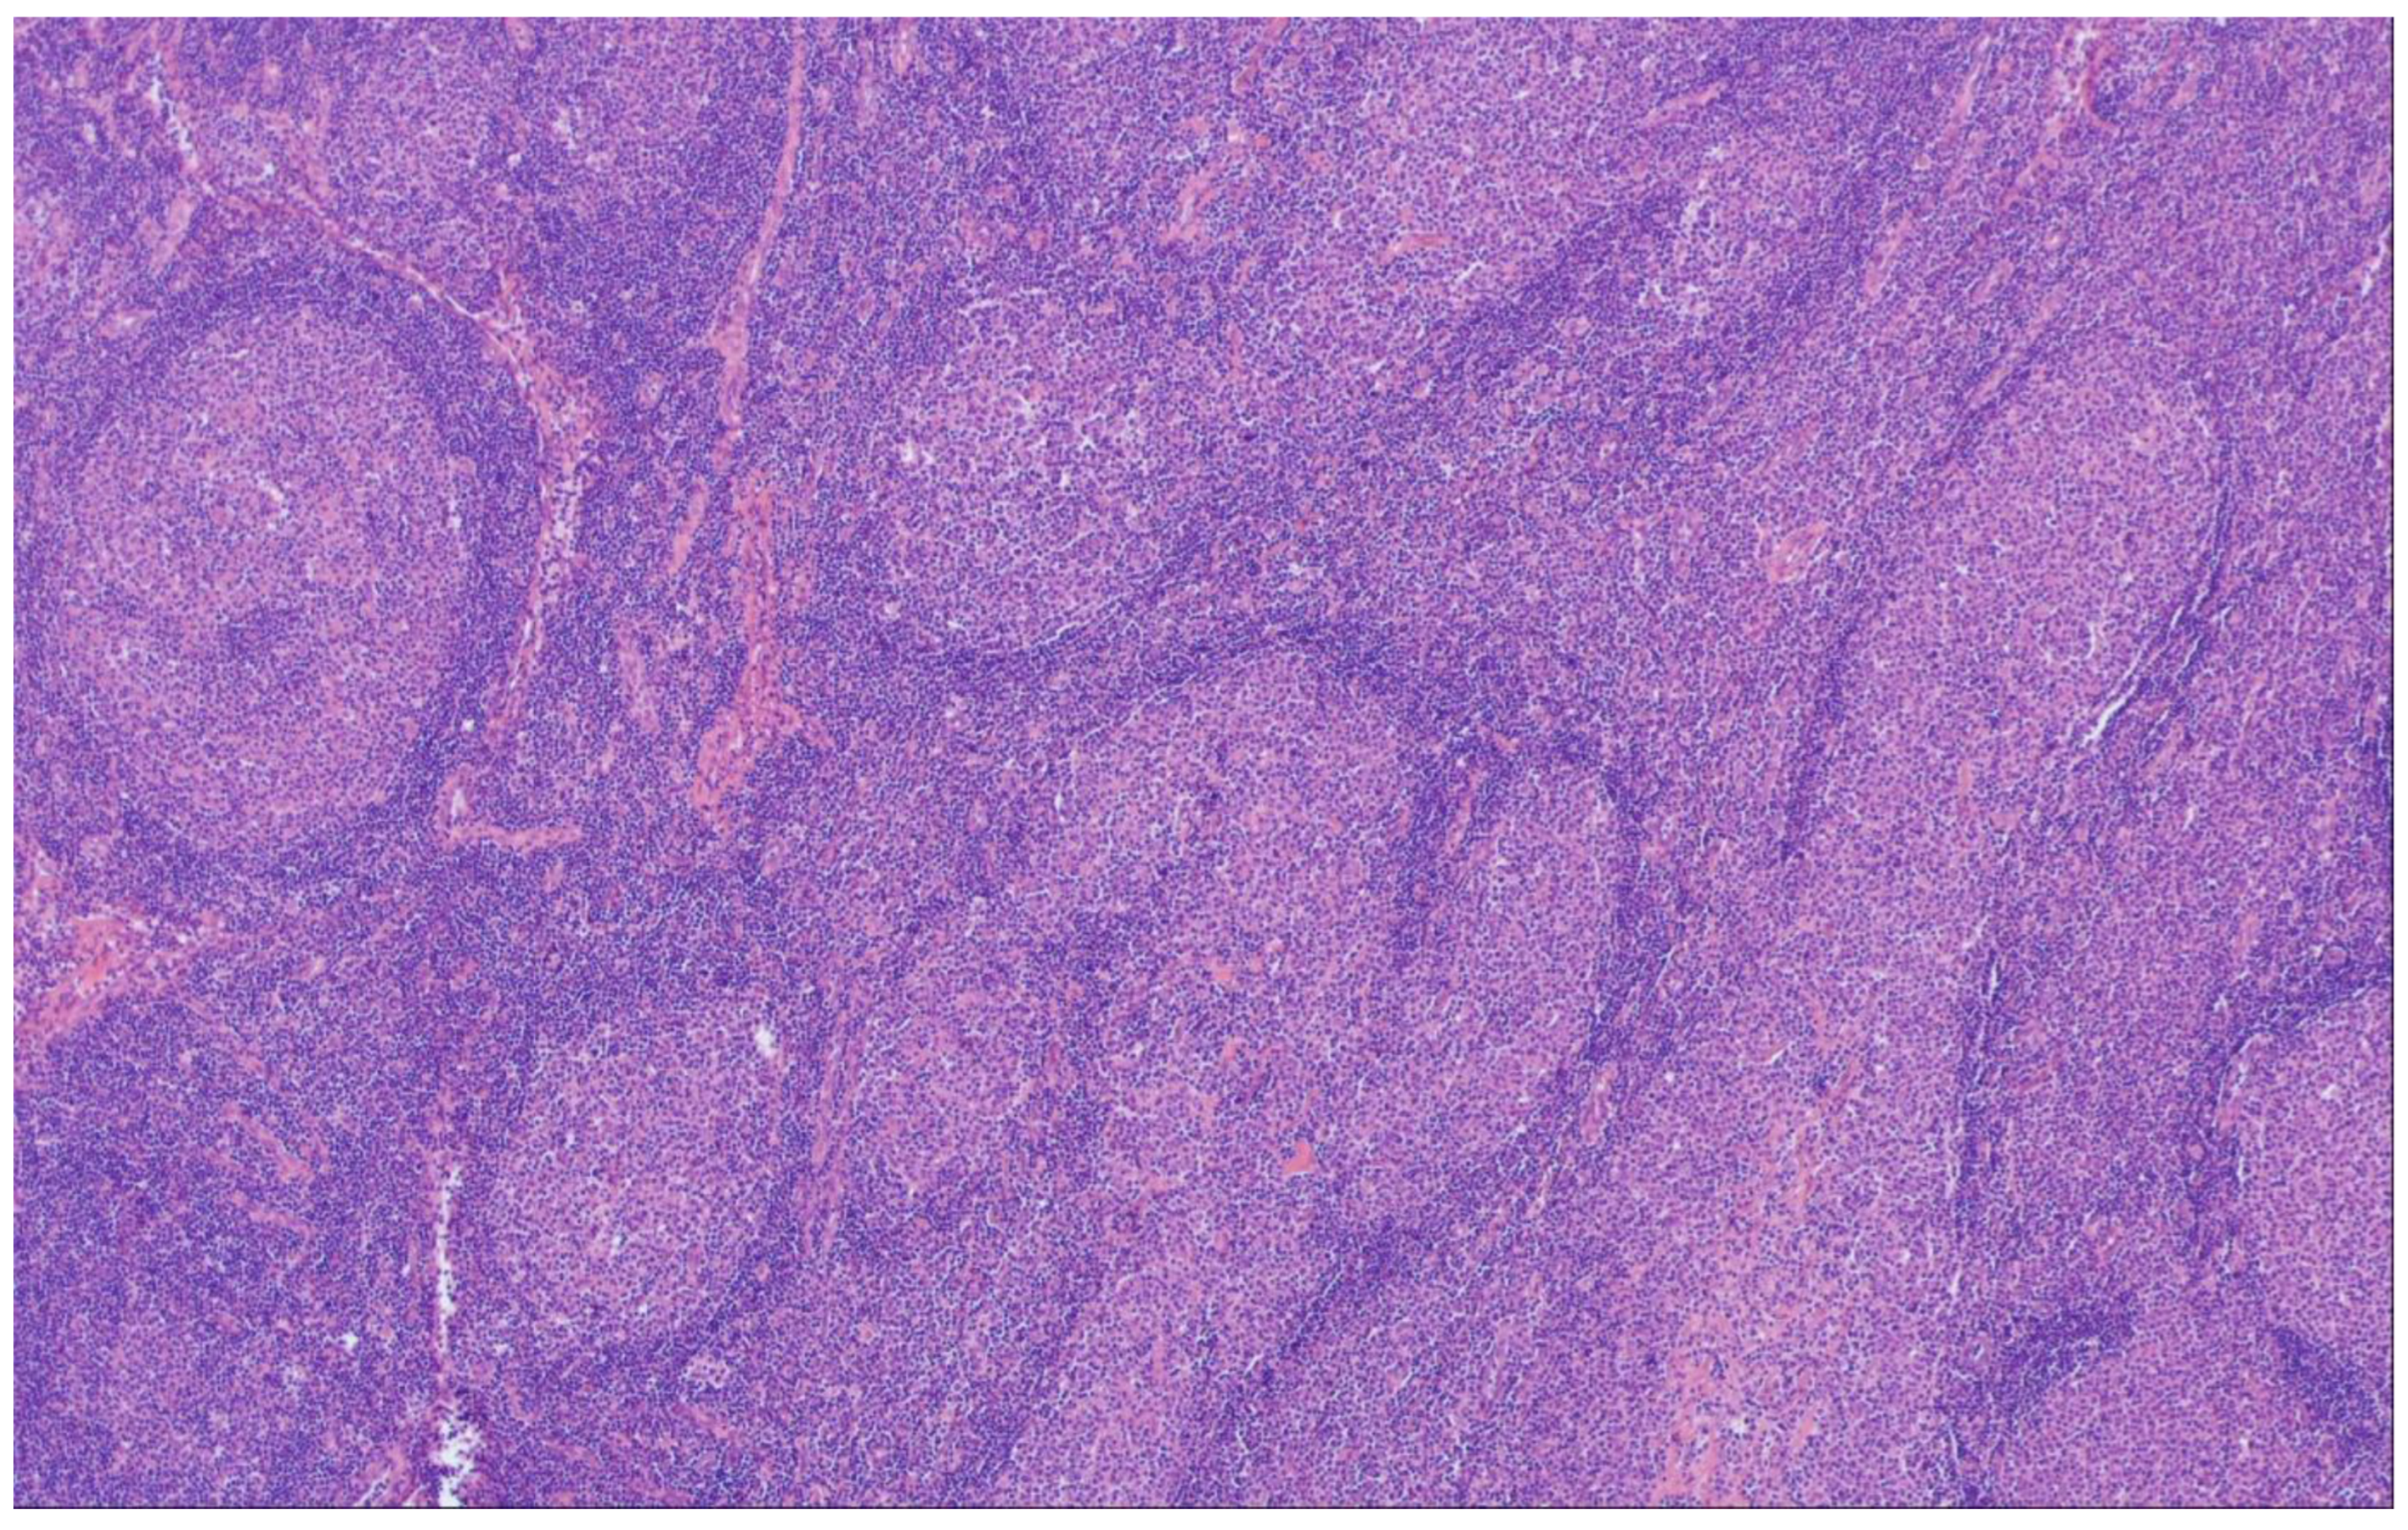

6. Predominantly Diffuse FL